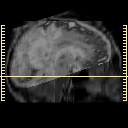

[Home][Help][Clinical] Slice 6

Click on sagittal image to select slice. Click on thin tickmark to change timepoint, or thick tickmark for overlay.